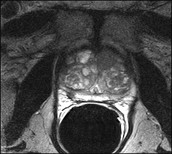

Η μαγνητική τομογραφία του προστάτη (mpΜRI, multiparametric magnetic resonance image) έχει πολύ καλύτερη ανάλυση μαλακών ιστών από το υπερηχογράφημα. Μπορεί να εντοπίσει περιοχές στον αδένα που είναι πραγματικά ύποπτες με υψηλό βαθμό ακρίβειας και αξιοπιστίας (θετική προγνωστική αξία μεγαλύτερη από 90%).

Η mpMRI χρησιμοποιείται επίσης για χειρουργικό σχεδιασμό σε άνδρες που εξετάζουν το ενδεχόμενο ριζικής προστατεκτομής.

Η πολυπαραμετρική μαγνητική τομογραφία του προστάτη έχει αποδειχθεί διεθνώς, σημαντική τόσο στη διάγνωση όσο και στην παρακολούθηση ασθενών με καρκίνο του προστάτη.

Μελέτες σε μεγάλα συστήματα υγείας του εξωτερικού έχουν αναδείξει την αξία της μεθόδου στον προληπτικό έλεγχο των ασθενών, στο λεγόμενο screening και τη διαστρωμάτωση κινδύνου, μειώνοντας το ποσοστό υπερδιάγνωσης κατά 72,6% και του αριθμού των απαιτούμενων βιοψιών κατά 53,5%.